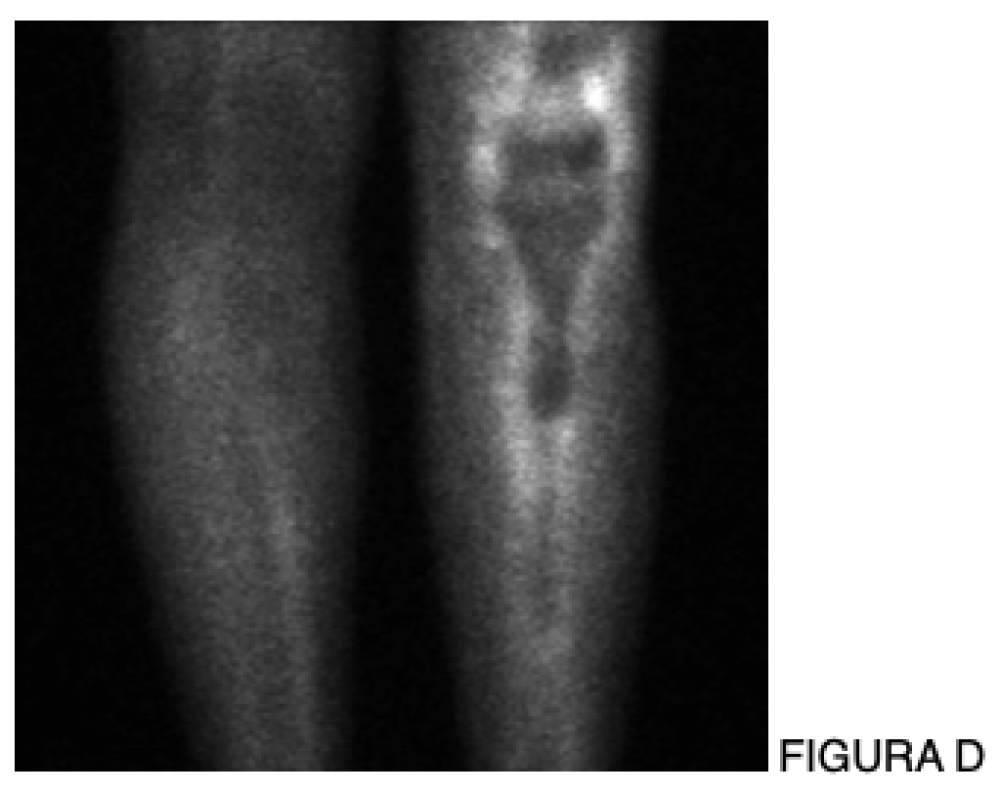

Seja nas artroplastias do quadril, joelho, ombro e tornozelo, seja nas endopróteses utilizadas no tratamento dos tumores ósseos, considero a infecção a complicação mais difícil de ser resolvida na Ortopedia.

Na Ortopedia Oncológica, esse cenário torna-se ainda mais dramático. Não raramente, o desfecho final de uma infecção profunda e refratária é a amputação, com impacto devastador para o paciente e para a equipe médica. Apesar disso, os princípios do tratamento da infecção são comuns a todos nós, independentemente da articulação envolvida ou da indicação original da prótese: profilaxia adequada, diagnóstico preciso, decisão cirúrgica correta e manejo criterioso da antibioticoterapia.

• Próteses não convencionais e oncológicas: incidência entre 10% e 25%, com maior gravidade clínica e impacto funcional [4,6].